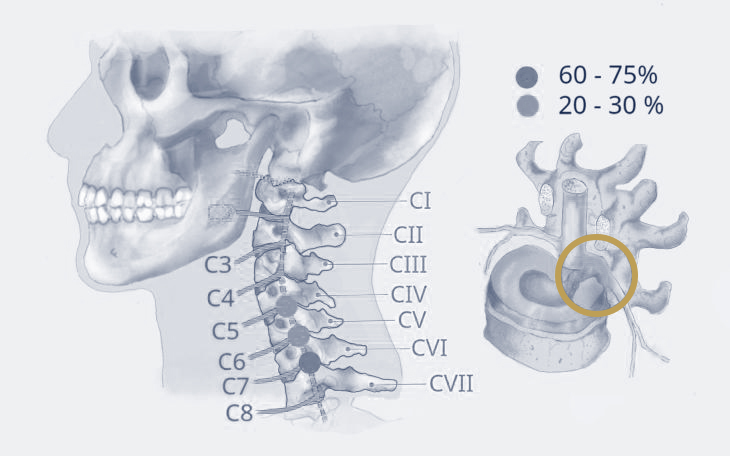

Erkrankungen der Halswirbelsäule

Die Halswirbelsäule (HWS) ist besonders beweglich und zugleich empfindlich gegenüber Fehlbelastungen und Verschleiß. In dieser Kategorie erhalten Sie einen Überblick über häufige Erkrankungen der HWS, deren Ursachen, Symptome und Therapiemöglichkeiten.

Bildquelle: www.docset.de